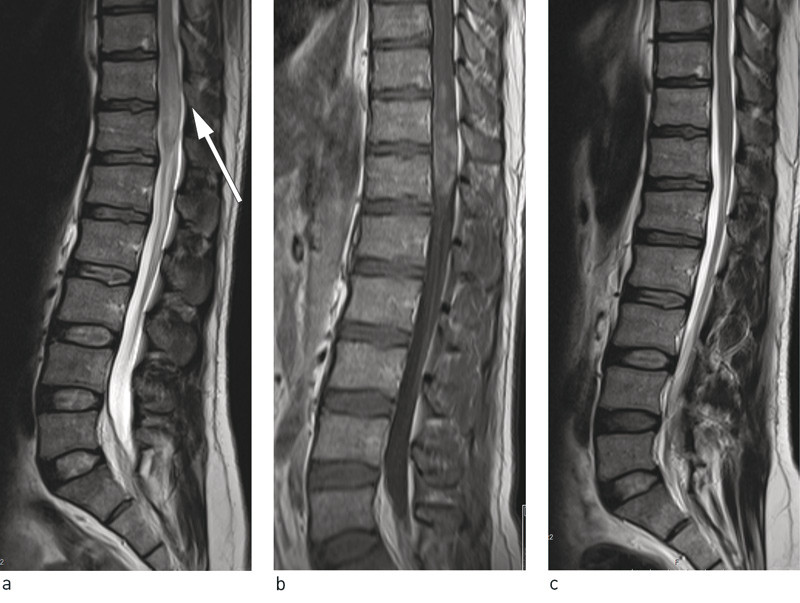

Spine MRI showed a pathological intramedullary lesion at level Th10/Th12 (Fig. 1a, b). In the distal medulla, a 6-cm-long spindle-shaped expansion was seen that extended to the conus. The lesion had an inhomogeneous signal, higher than that of the medulla on T2-weighted images. Use of contrast revealed patchy, inhomogeneous contrast enhancement. The medulla was so enlarged that it filled most of the spinal canal.

Figure 1 Lumbosacral spine MRI showing expansion of the medullary cone at level Th 11/Th 12 with hyperintensity on T2-weighted sequences and contrast enhancement on T1-weighted sequences. a) Sagittal T2-weighted sequence prior to treatment, b) Sagittal T1-weighted sequence with intravenous contrast prior to treatment and c) Sagittal T2-weighted sequence post-treatment

The findings were not typical of a solid tumour, transverse myelitis or demyelinating disease, although these could not be ruled out. On the basis of the images and clinical examination, we considered an infectious aetiology to be a highly relevant differential diagnosis, and the examining radiologist noted that schistosomiasis could have a very similar appearance. Tuberculosis was less likely because of the localisation and appearance of the lesion and because isolated involvement of the medulla is very rare.

Upon examination one year after discharge, he continued to have right-sided lumbar pain but this was less severe than prior to treatment for schistosomiasis. The patient stated that he had had problems with urination for the first three months, but that these had gradually resolved. He had no paresis. He described mild hypoesthesia in his lower right limb and mildly impaired vibration sense. The man was in occupational training and wished to return to work. An MRI showed complete regression of the previously observed lesion (Fig. 1c).

Assessment of schistosomiasis infection in hepatosplenic and urogenital organs can be performed using ultrasound, CT and MRI. Ultrasound can be used at the bedside and in the field and requires significantly less financial investment than the other modalities (8). CT scanning is particularly good for showing calcification of the urinary tract, which is typical of urogenital schistosomiasis (9). For ectopic infection with cerebral involvement or myeloradiculopathy, MRI is the optimal method. However, this modality is rarely available among the populations that are most at risk. In cases of neuroschistosomiasis, the distal medulla/conus is most frequently affected. On T2-weighted sequences, heterogeneous hyperintensities are seen along with expansion of the medulla, often over several segments. The presence of eggs and consequent granuloma formation may result in nodular contrast enhancement in the medulla and peripheral enhancement in the leptomeninges. In a number of cases there is also involvement of nerve roots and the cauda equina (10) – (12).